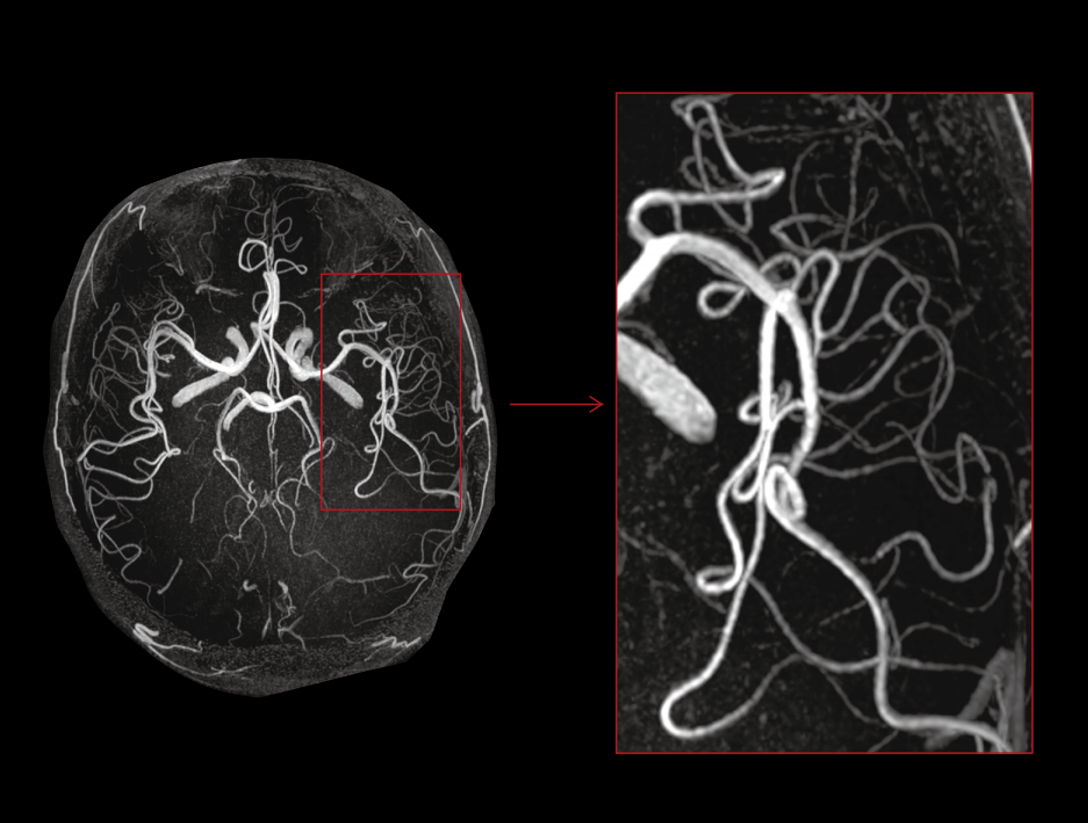

Potężny magnes 3,0 T ma krótką konstrukcję (170 cm), aby zapewnić wysoką jednorodność pola magnetycznego. Daje to solidne podstawy szybkiego obrazowania i doskonałego nasycenia tłuszczu w dużym polu widzenia, a także znakomitego obrazowania poza centrum.